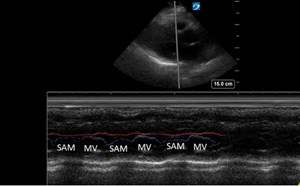

Advanced Echo Pocket Card Series #2: Diastolic Dysfunction

69-year old male with history of hypertension, diabetes, squamous cell carcinoma of larynx status post chemotherapy, radiation, total laryngectomy, tracheostomy dependence, and status post renal trans...